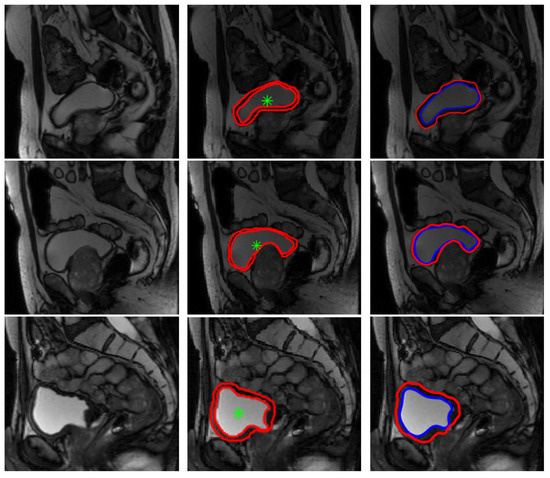

Segmentation results on our database were considered satisfactory by the medical team (some examples are presented in Figure 7 below). Manual segmentation considered as a ground truth was done by the medical team using a matlab algorithm that we have developed to be used by radiologists in our laboratory. As medical image segmentation is a crucial preprocessing step, comparing the quality of the semi-automatic segmentation with ground truth is an essential part. Therefore, in order to get a statistical validation, we have computed some metrics usually used for evaluating medical image segmentation, namely, Dice coefficient (DICE), mutual information and mean overall error rate, as shown in Table 1 below. The mutual information between two random variables [40] is defined as the measure of dependency between them. The Dice coefficient [41], called the overlap index and described in Equation (12), is the most used to validate medical segmentation:

Figure 7.

Examples of bladder wall segmentation results. Left column: original T2-weighted imaging. Middle column: bladder wall expert manual segmentation. Right column: Proposed Level Set approach segmentation results.